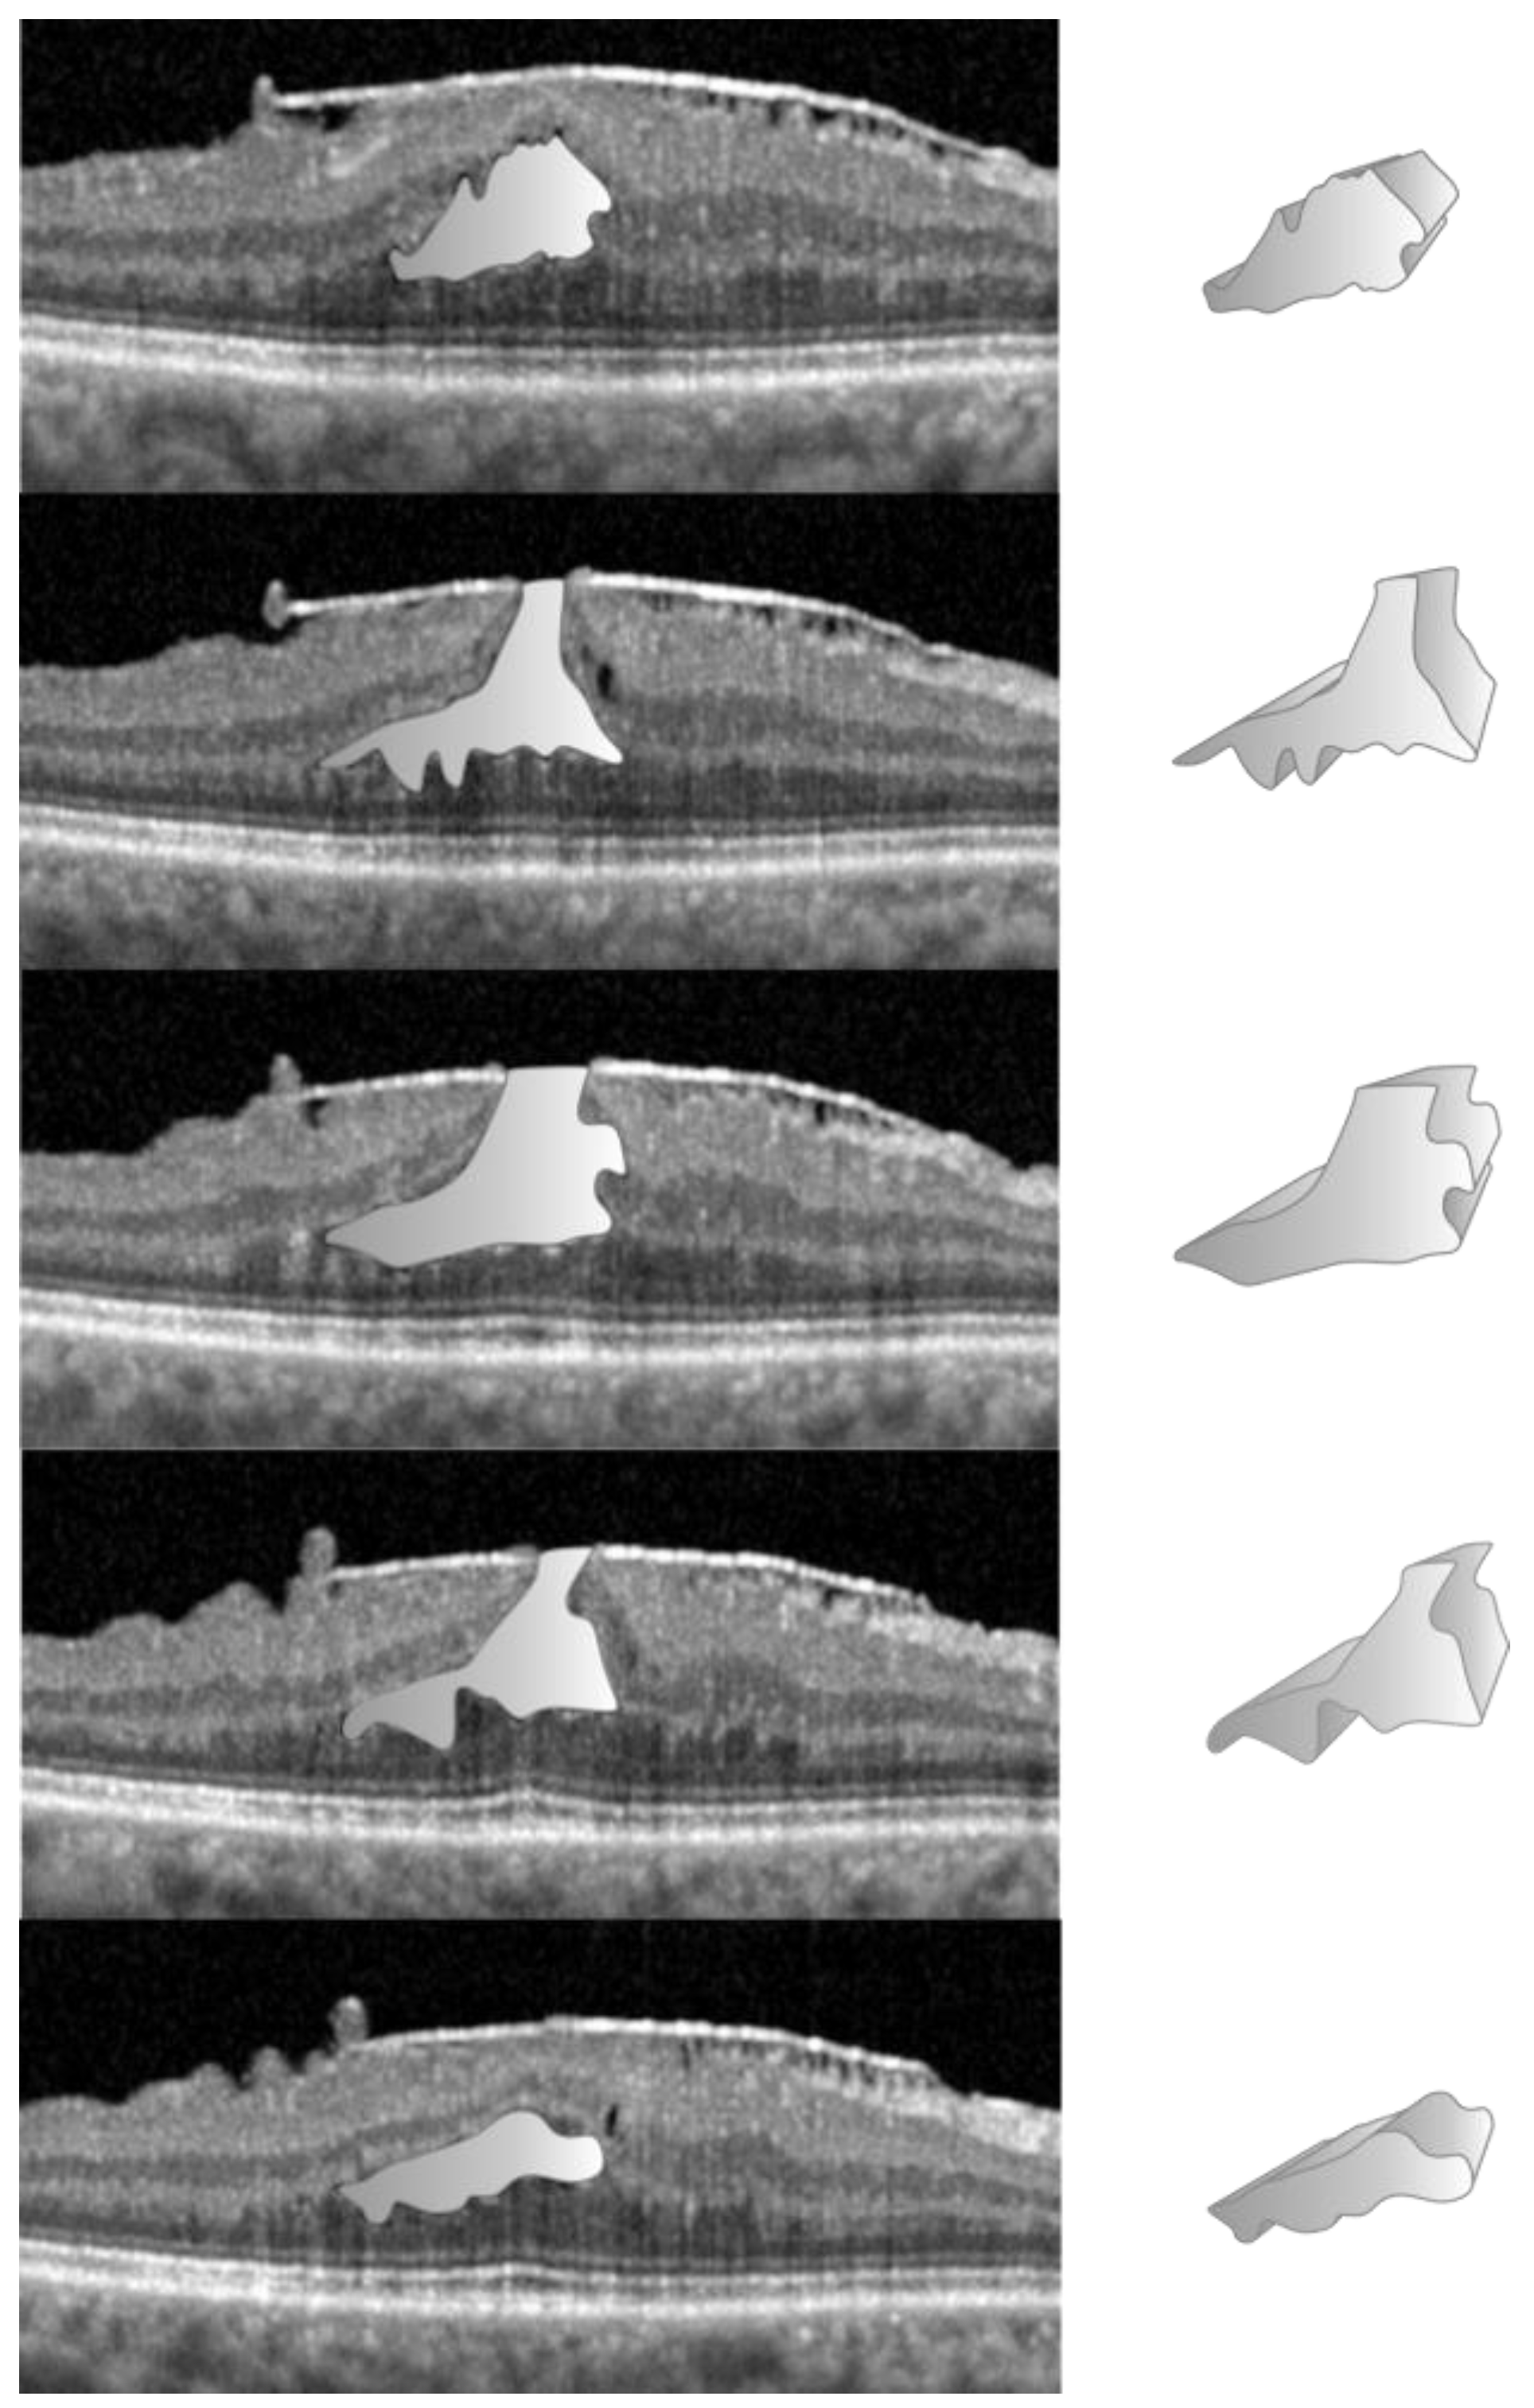

2. Materials and Methods

2.2. Data Acquisition in the NFP Group

2.3. Data Acquisition in the LMH Group

3. Results

4. Discussion